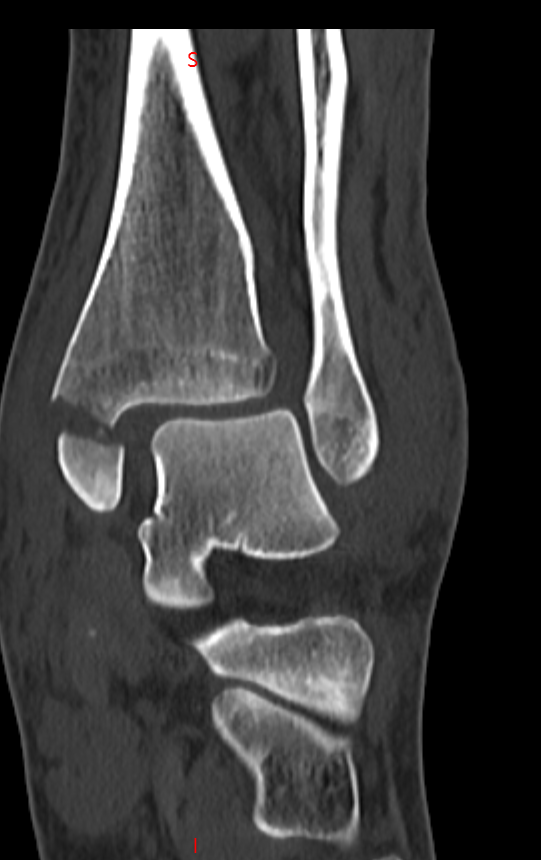

患者因意外受伤后踝关节疼痛、肿胀、无法行走,急诊就诊于成人ai 。

经检查确诊为旋前外旋 Ⅳ 度踝关节骨折,包含腓骨中段骨折、内踝骨折、后踝骨折及下胫腓联合分离,属于临床中结构复杂、稳定性破坏较严重的踝关节损伤。